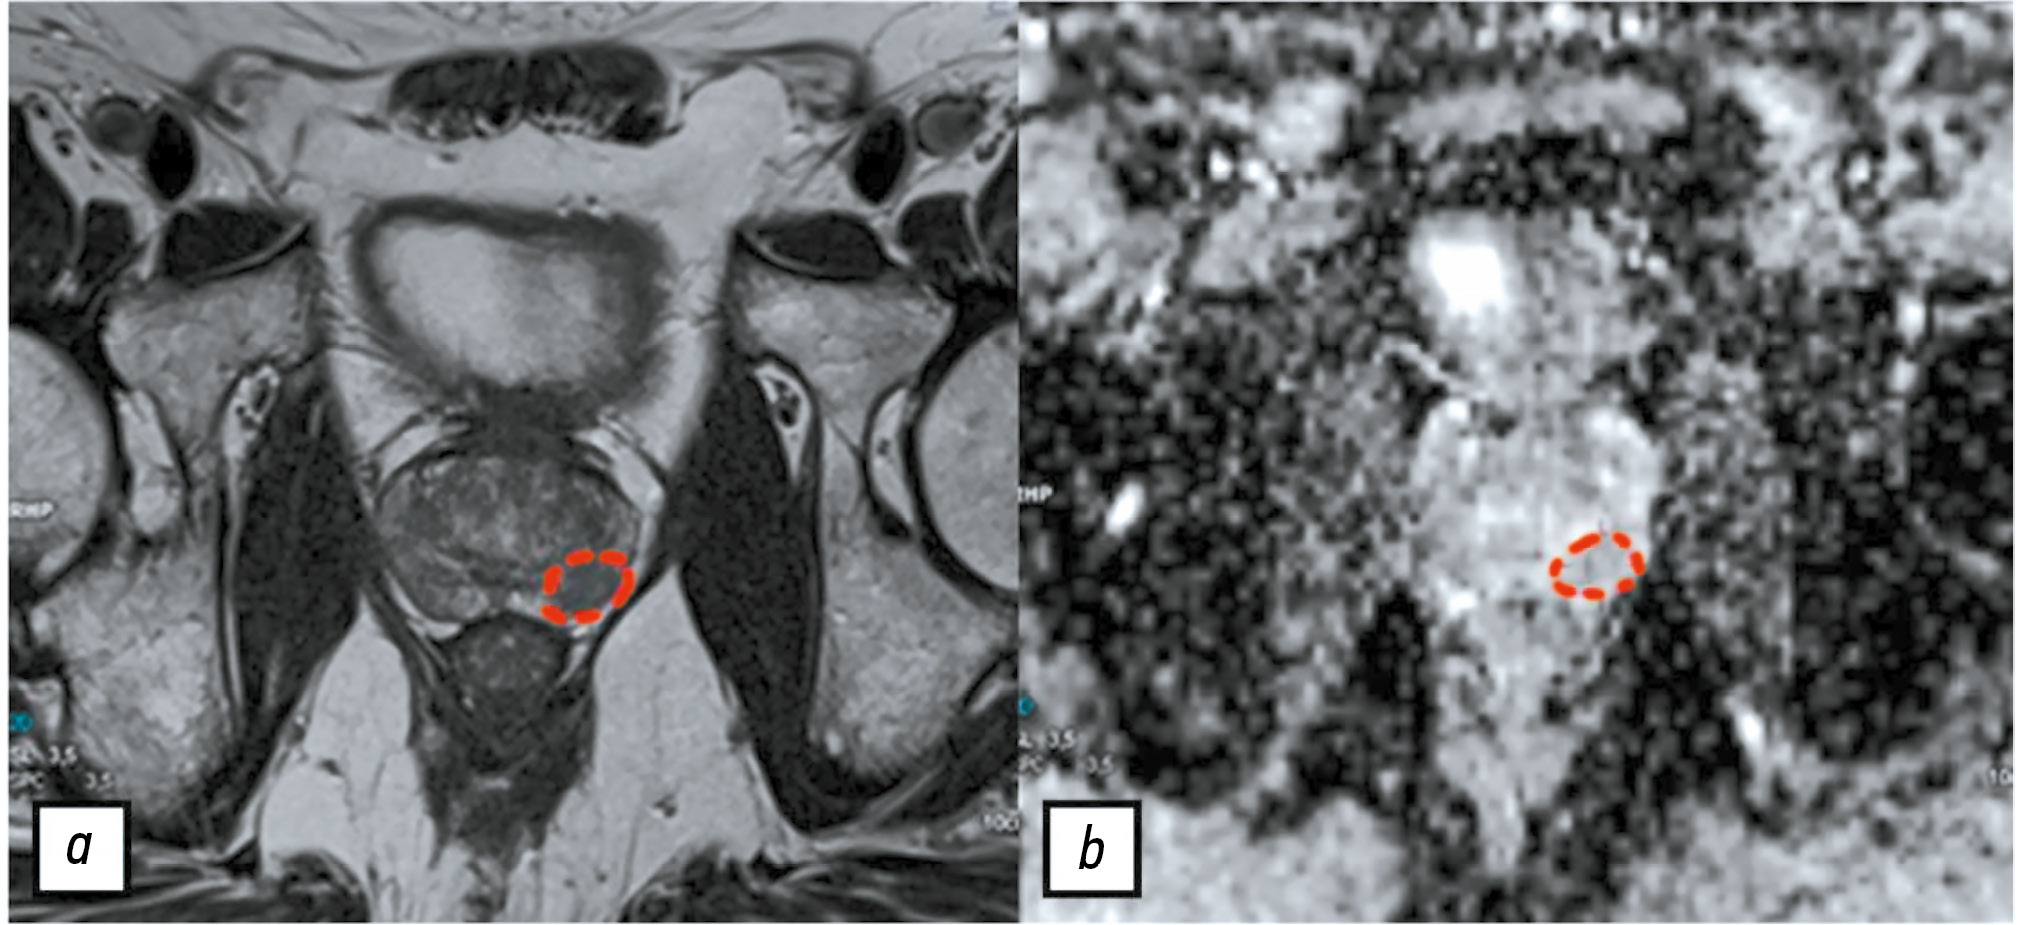

Consensus-based labeling algorithms for texture analysis of prostate lesions

Abstract

BACKGROUND: Texture analysis improves the diagnostic accuracy of magnetic resonance imaging and differential diagnosis of prostate lesions, which are primarily segmented through manual labeling, resulting in significant inter-expert variability of masks. A consensus-based technique can help reduce inconsistencies in prostate lesion segmentation. However, global scientific studies have not described any standardized, consensus-based labeling protocols.

AIM: This study aimed to develop a consensus algorithm for manual labeling of prostate lesions by several independent experts and evaluate inter-expert consistency in lesion segmentation.

METHODS: This retrospective study included 60 biparametric magnetic resonance imaging scans of the prostate gland performed according to PI-RADS 2.1 technical specification. The scans showed PI-RADS 3, 4, and 5 lesions. Two independent radiologists manually segmented the prostate lesions using 3D Slicer. Then, the resulting masks were compared using the Dice–Sørensen coefficient (DSC). For lesions with DSC ≥ 0.75, the final mask was based on the overlap between the two original masks. Conversely, for lesions with DSC < 0.75, the final mask was determined using the proposed consensus algorithm.

RESULTS: The proposed consensus algorithm significantly increased the DSC values, from 0.61 [0.48; 0.73] for primary labeling to 0.74 [0.62; 0.79] for labeling using the proposed algorithm (p = 0.01).

CONCLUSION: The proposed consensus-based algorithm for labeling prostate lesions using magnetic resonance imaging data is crucial in addressing inadequate approaches to objective segmentation in research and clinical settings.